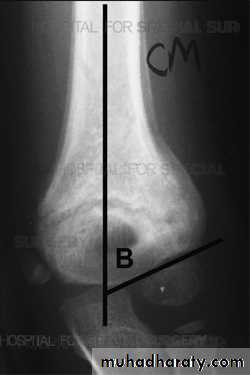

Supracondylar humeral fracture in children is one of the most common fractures seen in the pediatric orthopedic clinic setting worldwide. It's a fracture that occurs at the supracondylar area or the metaphysis of the distal humerus & accounts for 65.4% of upper extremity fractures in children .There are two types of supracondylar fractures in children according to direction of displacement of distal fragment i.e. extension type (97%) and flexion (3%).Immobilisation in an above-elbow backslab in 90 degrees elbow flexion with sling for 3 weeks. The backslab and sling should be worn under clothing (e.g. loose fitting shirt) and not through the sleeve